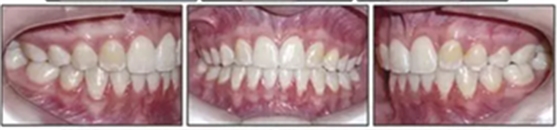

治療的總體目標(biāo)得以實(shí)現(xiàn)(圖8)??傊委煏r間為36個月。面部方面表現(xiàn)出充分的唇閉合和愉快的微笑。切牙運(yùn)動后有一些唇縮回。覆蓋和覆合良好,并且上下牙弓相協(xié)調(diào)(圖9)。I類磨牙關(guān)系得以實(shí)現(xiàn)。左側(cè)后牙反合得以矯正。下頜第二磨牙成功直立。

6年后治療結(jié)果保持穩(wěn)定(圖11,圖12 ; 圖13)??梢杂^察到穩(wěn)定的間隙關(guān)閉,正常的覆蓋和覆合,上下牙中線一致,微笑美觀。建議完美替代了拔除的側(cè)切牙。正畸治療后進(jìn)行牙齒美白。